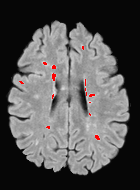

Patch size is another important parameter of the network. In computer vision applications such as object detection, usually a whole 2D image is used as a feature. However, full 3D medical images can not typically be used because of memory limitations. Fig. 4 shows examples of lesion memberships obtained with different sized 2D patches. As the patch sizes increases, the false positives that are mostly observed in the cortex tend to decrease. Fig. 5 shows a plot of Dice and LFPR with various patch sizes, ordered from left to right according to their increasing size. Note that smaller patches ( to ) produced significantly lower Dice and higher LFPR compared to other patches (), as seen from the memberships in Fig. 4. Also some of the highest Dice and lowest LFPR were observed for patches with large in-plane size, i.e., , , and . It was observed in Fig. 5 that there is no significant difference between Dice coefficients for , , or , but LFPR of both and are significantly lower than that of (). We chose as the optimal patch size. Other choices of smaller and patches (not shown) yielded worse results. Note that although training was performed with different patch sizes, the memberships were generated slice by slice, as the trained model consisted only of convolutions and did not need any information about patch sizes.

In our experiments, we used large 2D patches similar to Ghafoorian et al. (2017b), in comparison to isotropic 3D patches as used before, e.g., in Valverde et al. (2017), in Wachinger et al. (2017), and in Kamnitsas et al. (2017). The rationale behind using large anisotropic patches is twofold. First, experiments with full 3D isotropic or patches showed little or no improvement in Dice and led to increased false positives, with memberships similar to the one with patches, as shown in Fig. 4. Larger isotropic patches, e.g. or , showed inferior segmentation, and in some cases, optimization did not converge. The reason is that the FLAIR images in the test datasets had inherently low resolution in the inferior-superior direction, mm and mm compared to in-plane resolution of mm. Therefore 2D axial patches capture the high resolution in-plane information that represents the original thick axial slices. Second, the lesions are usually focal and small in size, unlike other brain structures. Therefore a very large isotropic patch around a small lesion can include superfluous information about the lesion, which can increase the amount of false positives. Note that with in more recent studies employing high resolution 3D FLAIR sequences, it is trivial to extend the algorithm to accommodate for 3D patches.